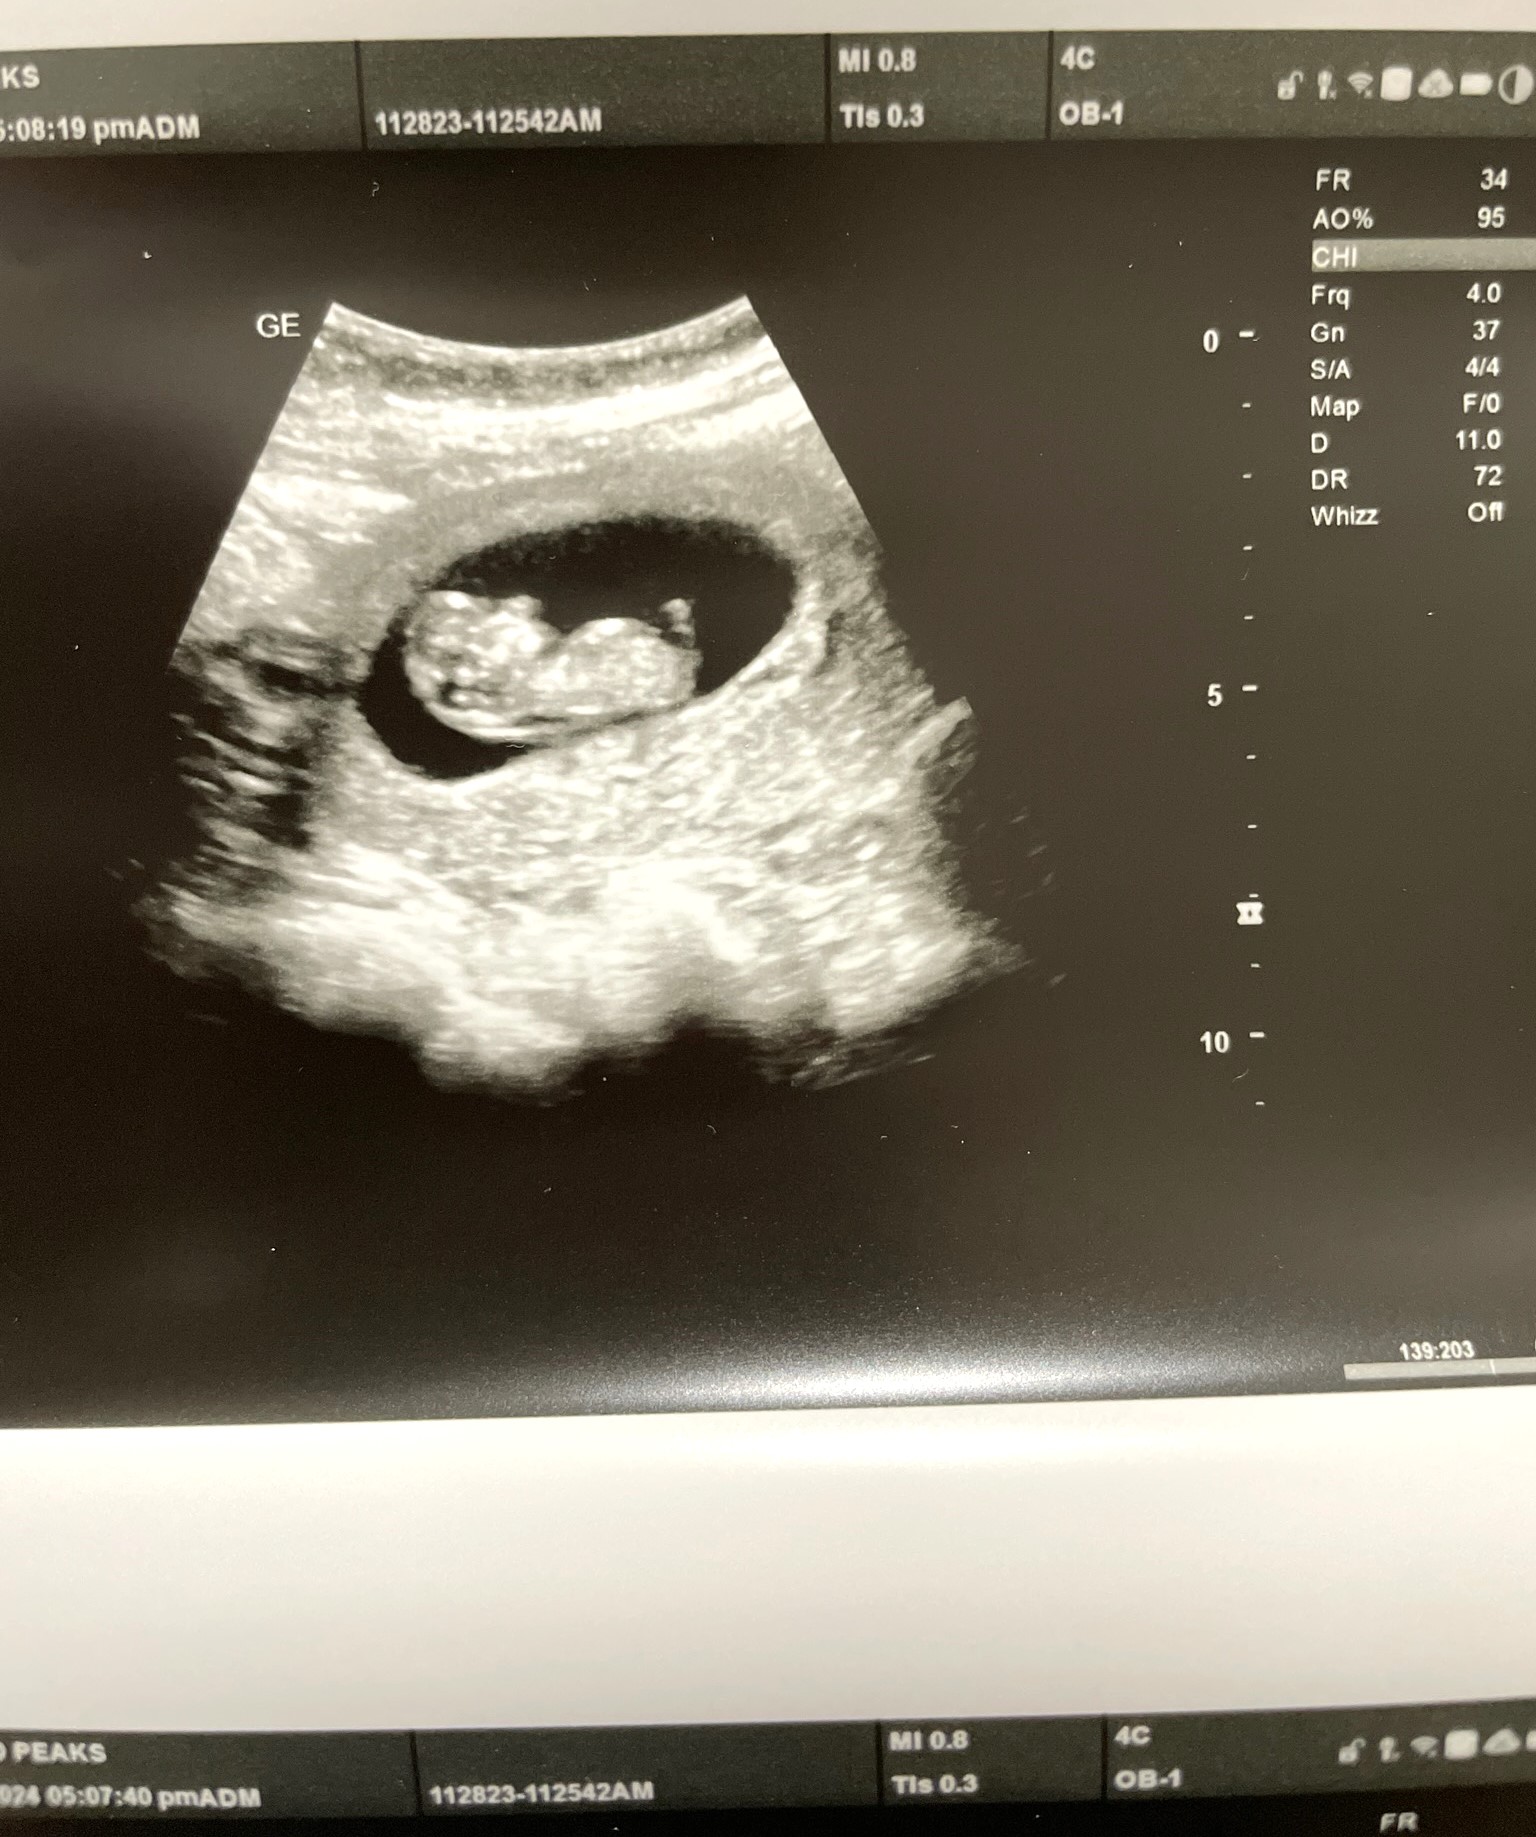

Katia and Skylar are expecting!

She (or he) is supposed to make her appearance on August 4th!

Katia has been suffering with morning sickness for the past 12 weeks.

Her sister has been helping by supplying red icees which she is able to keep down.